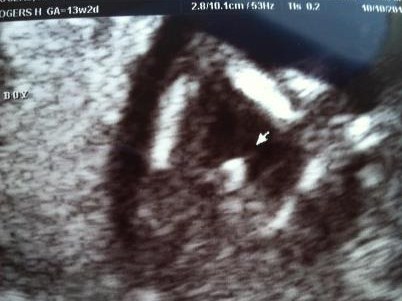

Great boy pics

Congratulations! Great pics